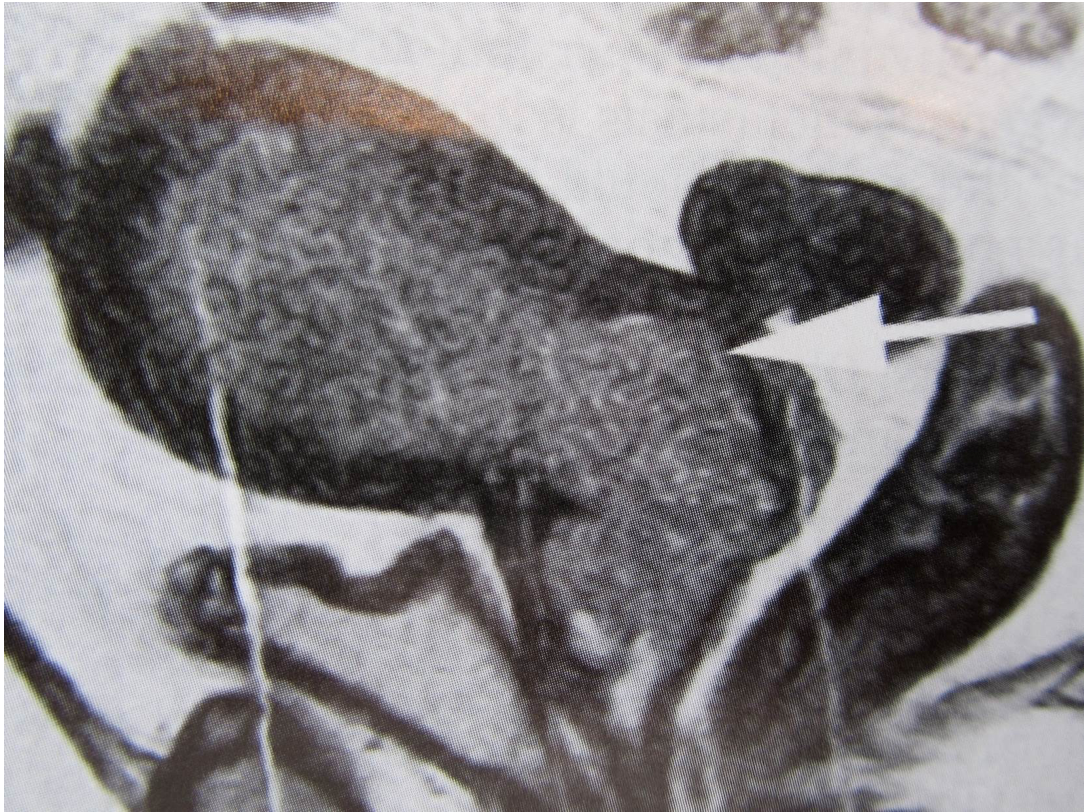

What this be?

Serous cystadenoma